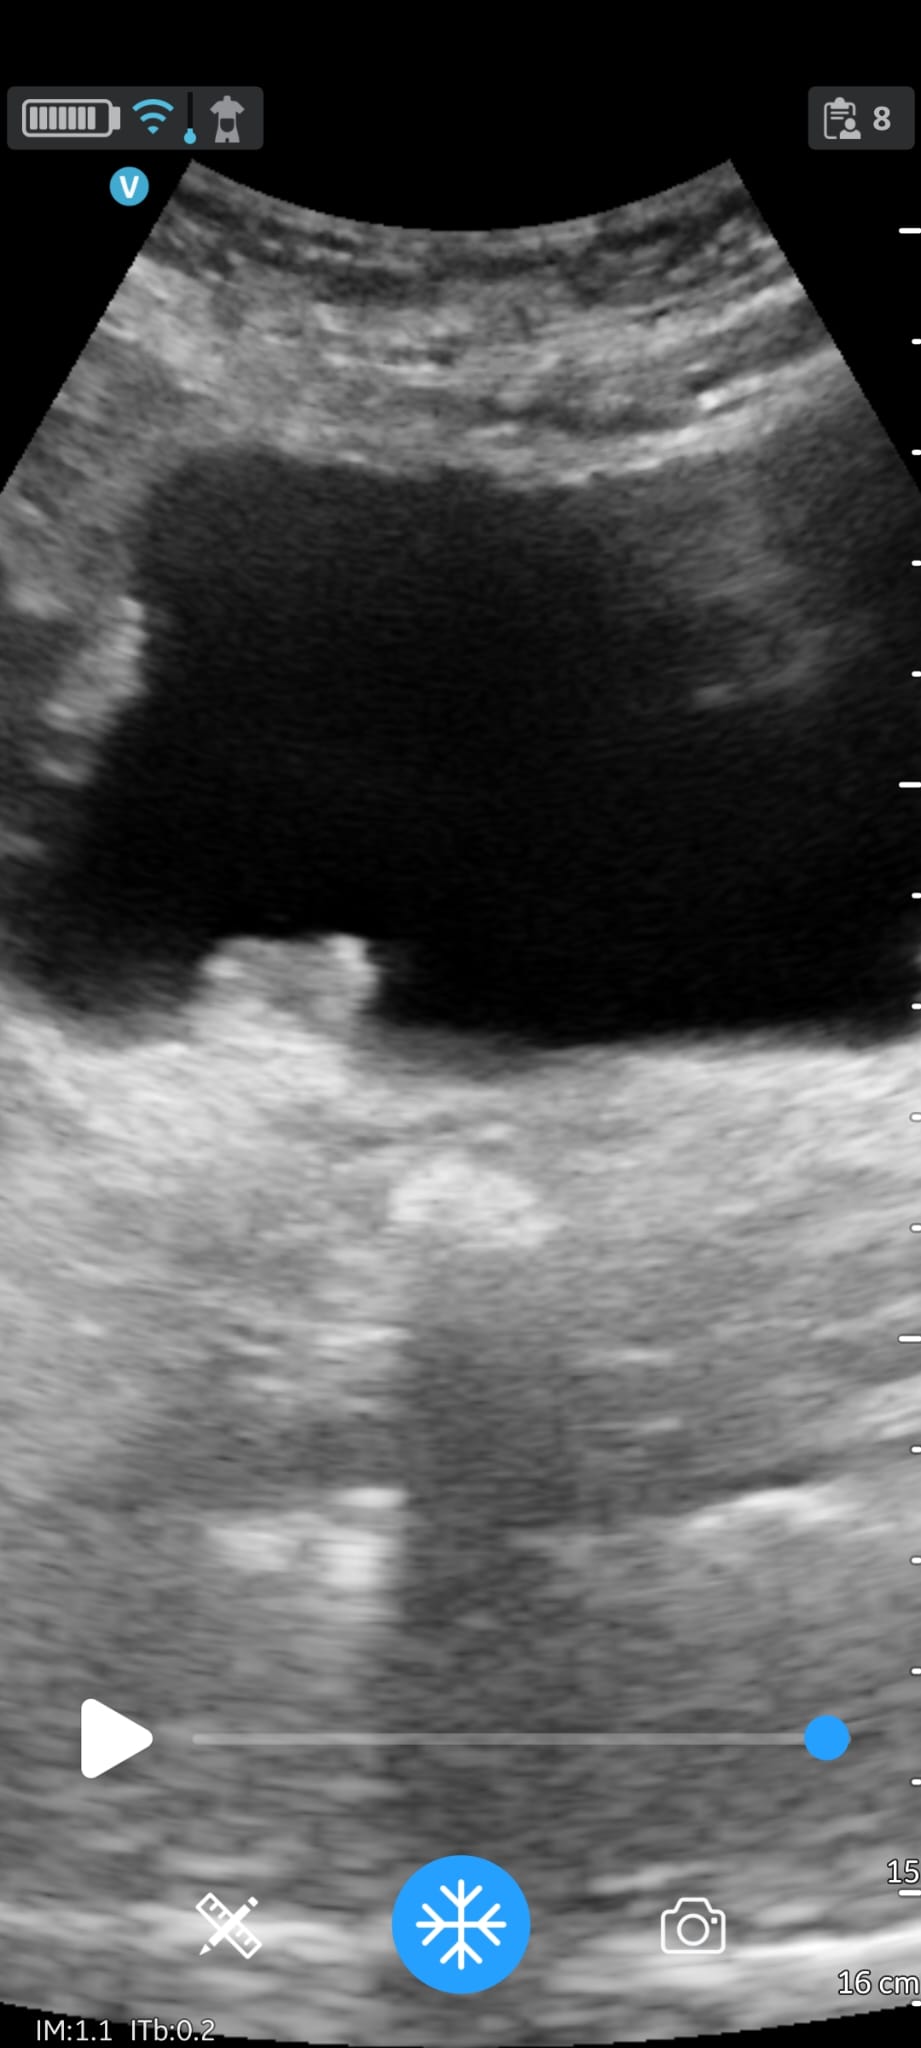

EcoAP imagen excrecente ureter derecha vejiga (coincide con TAC aún no valorado urología).

28/06/2024 TC pared vesical meato de 2 lesiones que captan contraste de 7 y 10 mm.

Neoplasia vesical.